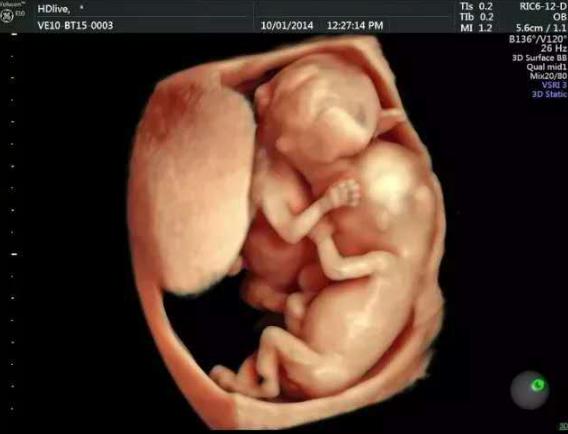

其实,就像朋友这样,怀孕四个多月了,那宝宝畸形的概率还是很大的,但具体影响有多大,还是要做个四维彩超才知道。

四维彩超是在怀孕24周左右做的,可以筛查胎儿颜面畸形、内脏畸形、四肢畸形等,而她现在是怀孕四个月,也就是怀孕16-18周了,我让她提前咨询医生,预约四维检查了。